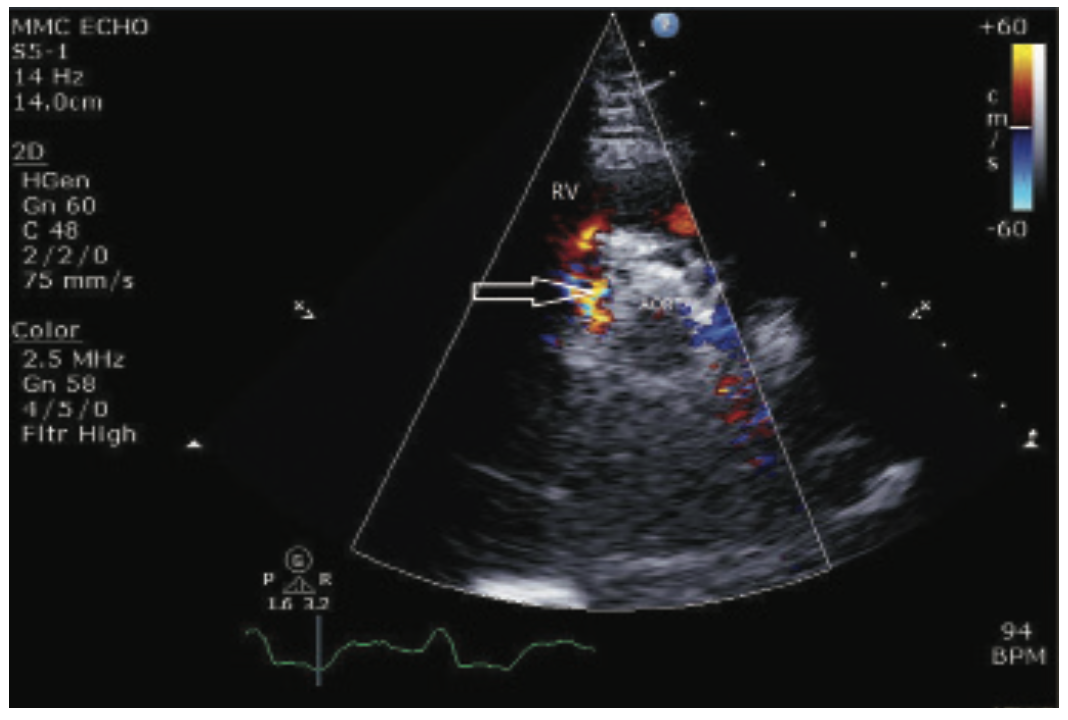

The TAVR procedure was performed one month later via right femoral access using the standard technique. Pre-dilatation with a 22 mm balloon was required, due to severe calcification of the valve leaflets. A 29 mm CoreValve Evolut (Medtronic) was advanced and appropriately positioned. A severe paravalvular leak was noted after valve deployment. Three serial dilatations were performed with 24 mm, 25 mm, and 28 mm balloons, respectively. Intraprocedural imaging revealed a mild paravalvular leak with a new severe central valvular leak, likely secondary to serial balloon dilatations. A second 29 mm CoreValve Evolut was subsequently deployed 3-4 mm above the initial valve with an excellent result. A transesophageal echocardiogram (TEE) revealed a small fistula between the aortic root and the right ventricle without a significant shunt. On the table, the patient developed complete heart block with a junctional escape rhythm. A temporary pacemaker was inserted, and he was monitored on telemetry throughout recovery. The following day, a permanent pacemaker was placed, secondary to persistent third-degree heart block. Post-operative TTE showed a normally functioning bioprosthetic valve, trace aortic regurgitation, calculated AVA 2.5 cm2, and a mean gradient of 6 mmHg. A fistula between the aortic root and RV was confirmed and unchanged. Mildly increased velocity across the pulmonic valve was noted without a change in RV pressure.

The patient remained asymptomatic post-procedure and was discharged on hospital day five. He had an otherwise uneventful hospital course. At 30-day follow-up, the patient denied dyspnea, orthopnea, or lower extremity swelling. He reported an increase in exercise tolerance and his physical exam did not yield any evidence of heart failure. Repeat TTE illustrated a stable aortic to RV fistula without hemodynamic changes. The patient continues to be managed conservatively with repeat imaging and clinical evaluation three years post procedure.